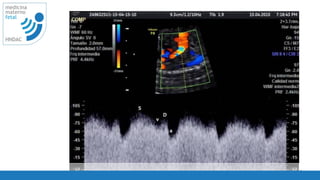

PRF adecuado

velocidad de barrido

PRF